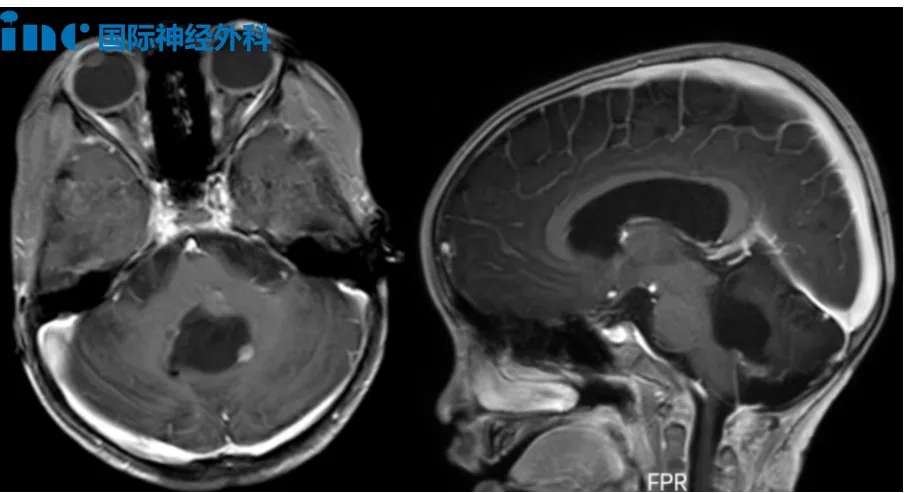

5岁男性患儿布布,2023年因行走不稳发现颅内占位,同年9月接受首次第四脑室肿瘤切除手术,术后病理诊断为后颅窝室管膜瘤。2024年5月因肿瘤复发接受二次手术,病理升级为间变性室管膜瘤(WHO 3级)。术后出现斜视、眼炎、四肢无力、共济失调、吞咽障碍及言语迟缓等症状。2024年9月完成质子放疗后,近期复查提示术区边缘出现可疑结节,粘连延髓,疑似再次复发。巴特朗菲教授评估认为肿瘤位于脑干背侧表面,未深入脑干内部,手术可及性良好,建议手术治疗。

61岁女性患者鲁女士,2003年7月因左侧额部麻木疼痛、额纹消失,发现脑干三叉神经区脑膜瘤,行开颅手术后肿瘤残留,相继出现视物颠倒、复视,伽玛刀治疗后发生左侧肢体麻木、乏力。2012年复查提示脑膜瘤复发,行第二次伽玛刀治疗。2018年以来逐渐出现左侧耳鸣、左侧面部持续性麻木疼痛,2025年症状加剧。巴特朗菲教授表示手术将力争最大程度切除肿瘤,同时保护神经功能。